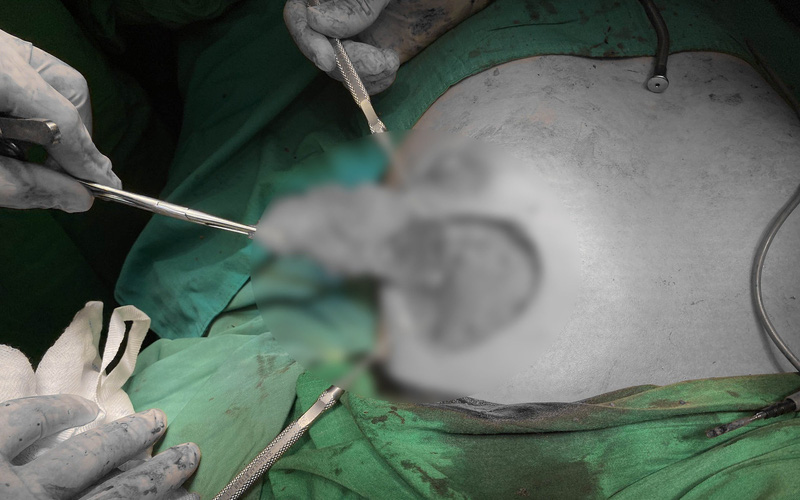

Tại đây, các bác sĩ xác định bệnh nhân bị nhiễm trùng ở vùng ngực và mô tuyến vú. Ekip điều trị đã tiến hành phẫu thuật, bóc tách lớp mỡ tự thân được cấy vào vào xử lý lại từ đầu cho vùng phẫu thuật.

Bệnh nhân bị biến chứng sau khi nâng ngực bằng mỡ tự thân tại một cơ sở làm đẹp qua lời giới thiệu của một người bạn. Ảnh: BVCC